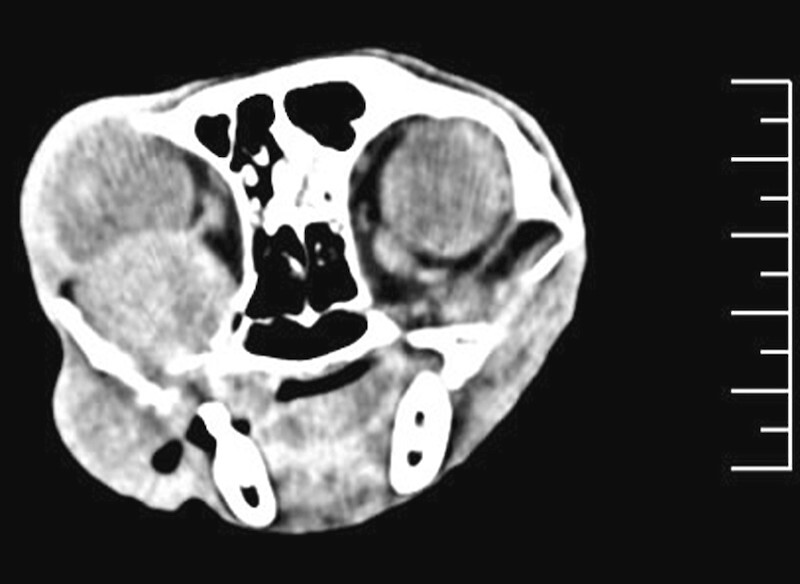

Die Modalität der Wahl bei Neoplasieverdacht ist die Computertomografie (CT) [8] . Als Schichtbildverfahren kann mittels CT eine Aussage über Größe, Lokalisation, Ausmaß, Invasivität der Veränderung und die regionalen Lymphknoten getroffen sowie geeignete Biopsieorte identifiziert werden [8] ( [Abb. 6] ). Die Möglichkeit zur multiplanaren Rekonstruktion stellt eine wichtige Unterstützung für die Planung von Resektionen oder Bestrahlung dar.

Dentale Röntgenaufnahmen sind gut geeignet zur Darstellung kleinerer Kieferabschnitte, ersetzen jedoch bei der diagnostischen Aufarbeitung von oralen Neoplasien nicht die Computertomografie. Die bei felinen Zahnpatienten routinemäßig angefertigten intraoralen Dentalröntgenaufnahmen aller Kieferabschnitte geben einen guten ersten Überblick über die Läsionen. Zahnröntgenaufnahmen sollten deshalb ohne Ausnahme angefertigt werden, auch von nicht zahntragenden Kieferabschnitten, um keine Befunde zu übersehen. Das Röntgenbild eines Patienten mit mandibulär lokalisiertem Plattenepithelkarzinom zeigt bereits die Destruktion des Knochengewebes mit Verlust der Kortikalis, während erst die Computertomografie das Ausmaß und die Ausdehnung der Läsion zeigt ( [Abb. 7] und [8] ).